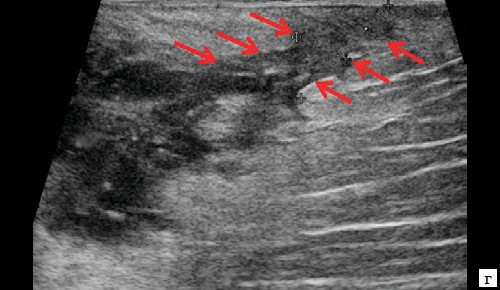

При УЗ-исследовании мягких тканей промежности выявлено: в перианальной области слева в проекции пальпируемого уплотнения на 2-3 часах по условному циферблату ближе к анальному каналу на глубине 0,6 см от поверхности кожи определяется гипоэхогенное жидкостное образование с четкими неровными контурами с наличием неоднородного гиперэхогенного подвижного содержимого размером 3,9×2,1×1,9 см, объемом 8,24 мл с утолщенными до 0,3 см стенками.

Описываемое образование прилежит к передне-боковой утолщенной стенке анального канала, нечетко от нее дифференцируется (см. рис. 1, а, б). По периферии образования – выраженная сосудистая реакция (см. рис. 1, в). По периферии образования ближе к ягодичной области – формирующийся свищевой ход размером 1,3×0,6×0,6 см (см. рис. 1, г).

Рис. 1. а, б – В-режим. В перианальной области слева на глубине 0,6 см от поверхности кожи определяется гипоэхогенное жидкостное образование с четкими неровными контурами с наличием неоднородного гиперэхогенного подвижного содержимого размером 3,9×2,1×1,9 см, объемом 8,24 мл с утолщенными до 0,3 см стенками. Описываемое образование прилежит к передне-боковой утолщенной до 1,0 см стенке анального канала, нечетко от нее дифференцируется (стрелки);

в – режим ЦДК. В подкожно-жировой клетчатке по периферии образования отмечается обогащение сосудистого рисунка;

г – В-режим. По периферии образования ближе к ягодичной области – формирующийся свищевой ход размером 1,3×0,6×0,6 см (стрелки).